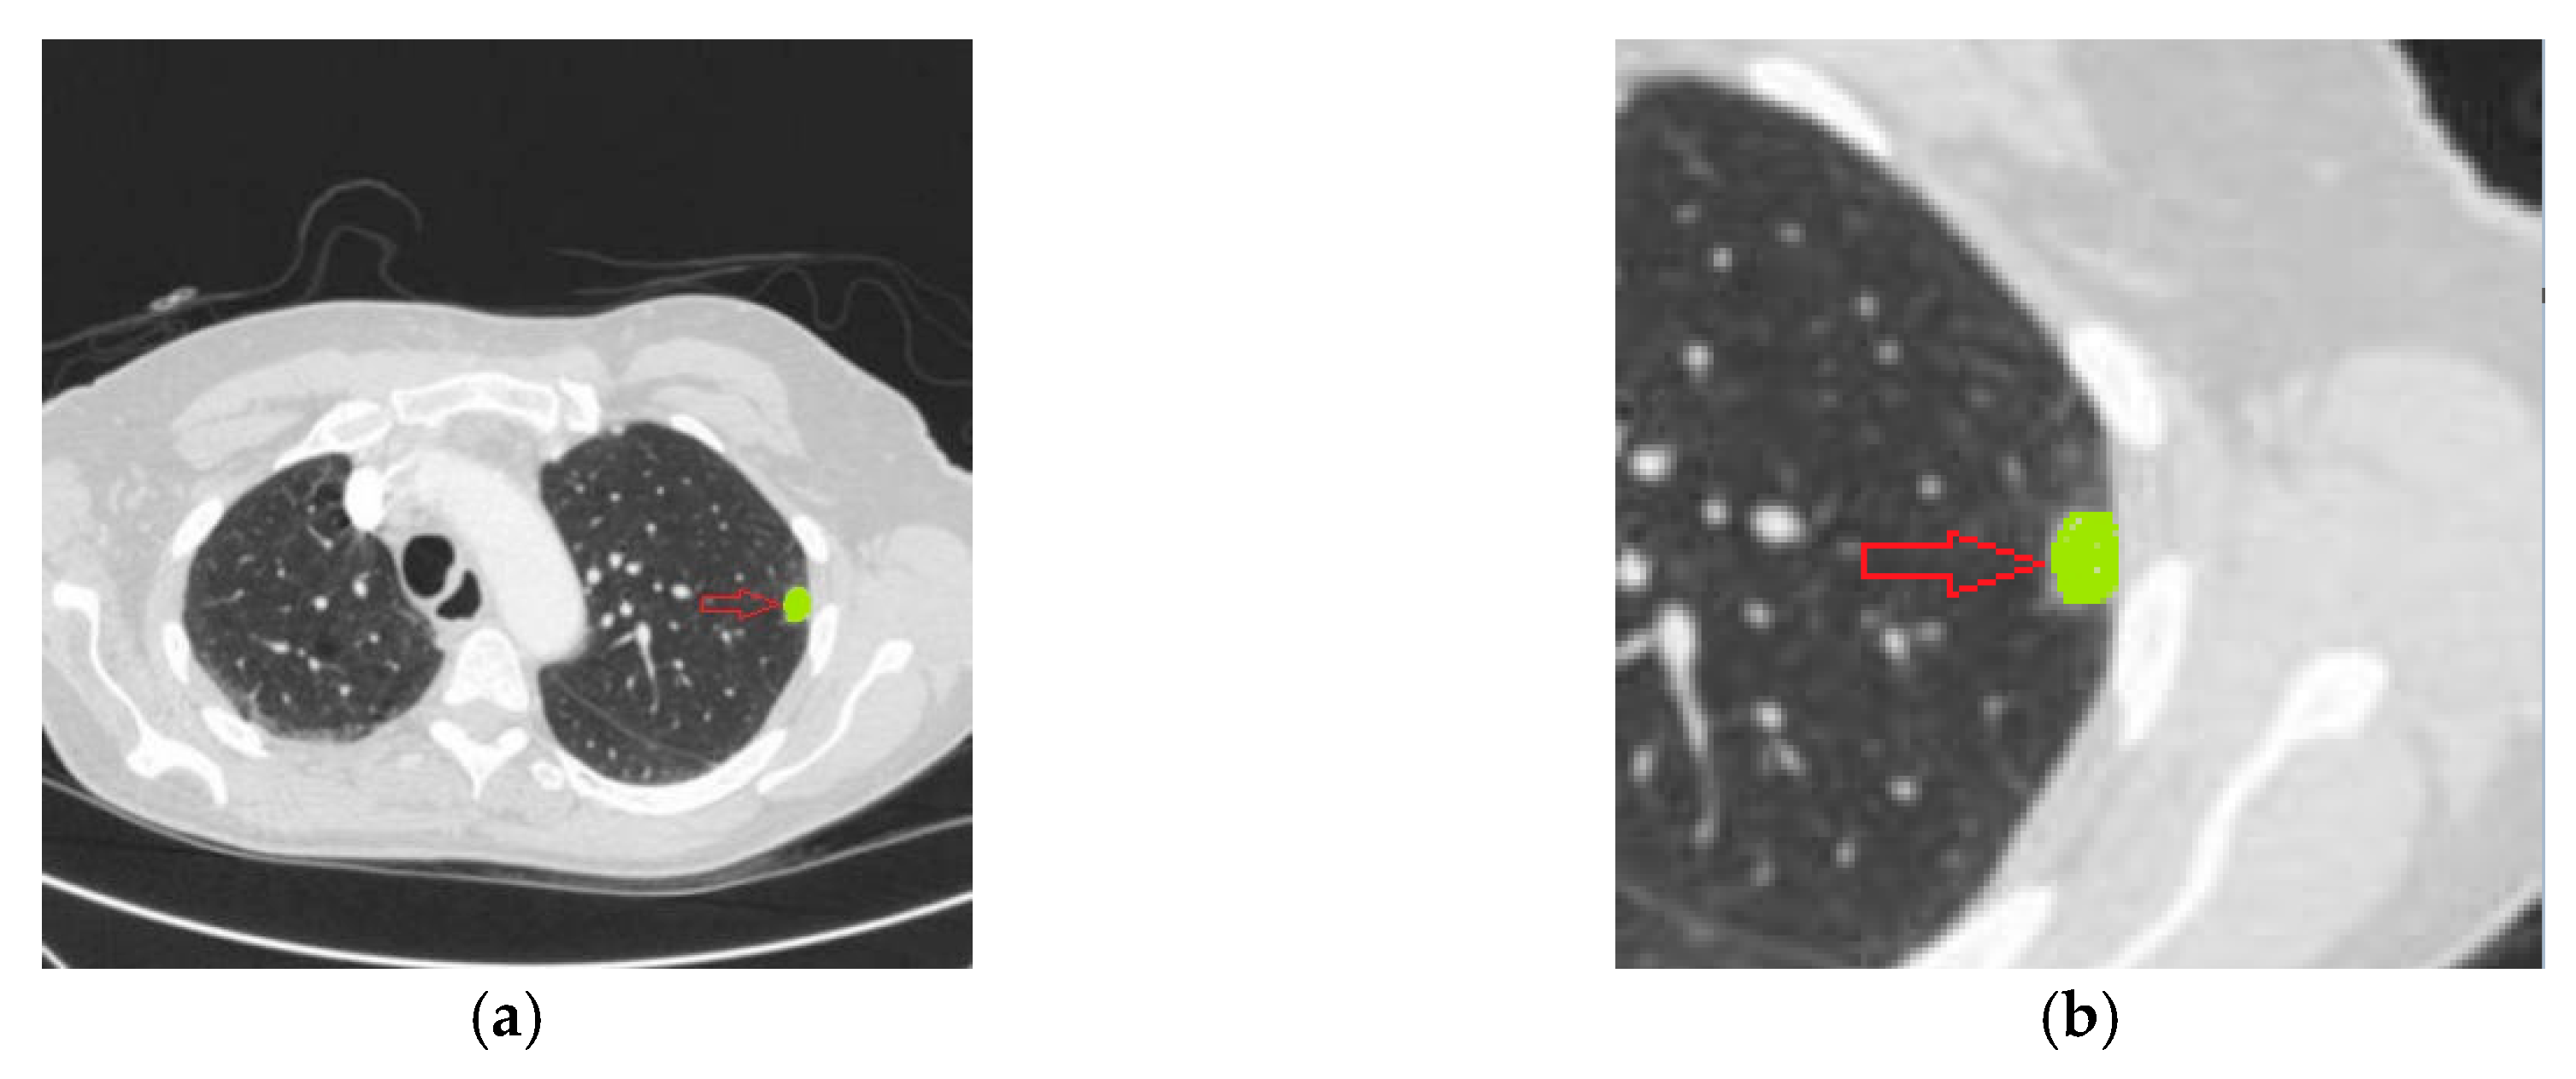

3.2. 2-Type Nodule Classification